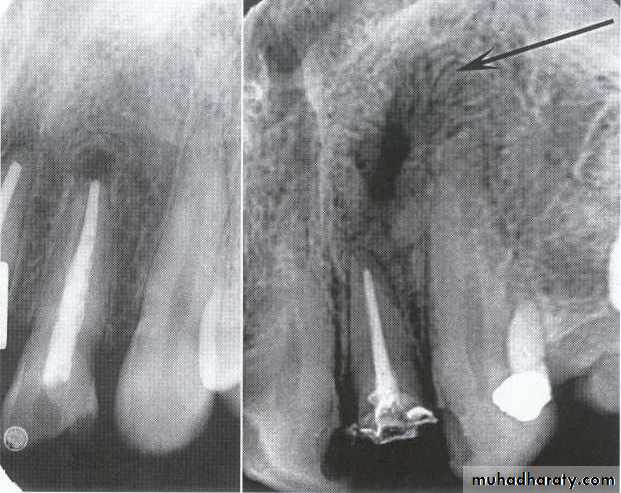

Radiolucency at apex of endodontically treated tooth

A: Radiolucent apical scar left after successful endodontic treatment..

B:New bone forming from the periphery of the

Lesion.

If the R.L.enlarged, pain,sinus,or no regression in the size of lesion after 6months (P. A. Cyst).

A

B

Apical scar